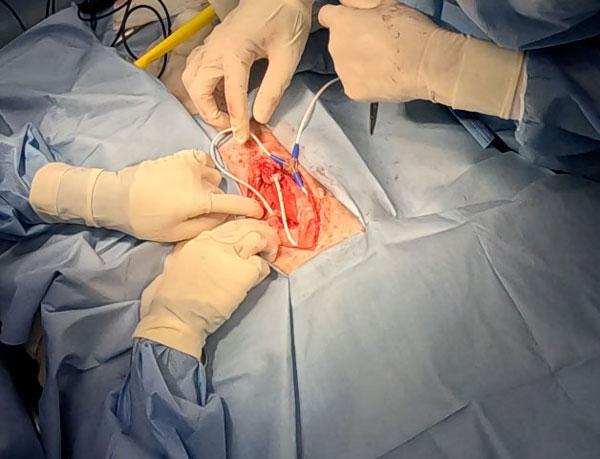

手術紹介

胆嚢摘出